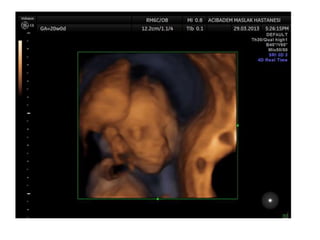

Binder Phenotype

a flat profile and depressed nasal bridge.

Short nose, short columella, flat naso-labial angle and

perialar flattening

Isolated Binder Phenotype transmission would be

autosomal dominant

Binder Phenotype can also be an important sign of

chondrodysplasia punctata (CDDP)